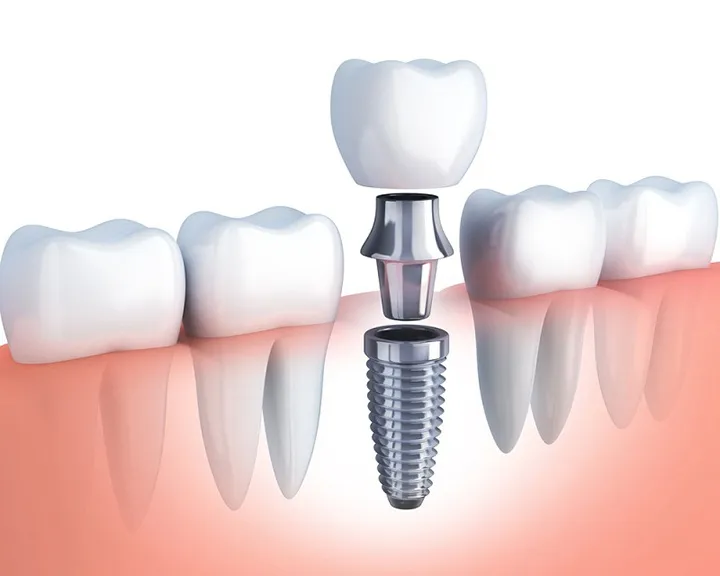

Mất răng là tình trạng phổ biến có thể xảy ra do sâu răng, viêm nha chu, chấn thương hoặc tuổi tác. Không chỉ ảnh hưởng đến